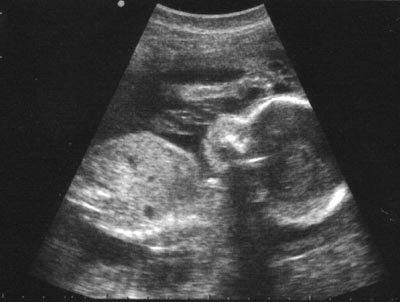

Obstetric Scan

Obstetric scan produced to determine the position of pregnancy, number of child present and gestational age of fetuses. It has seen the picture of the inside body using sound waves. Obstetric scan is safe and painless for mother and child. It is also called ultrasound scanning or sonography. It has a high frequency sound waves are transmitted into the body through the gel. Obstetric scan is a medical test that helps doctors diagnose and treat medical conditions.